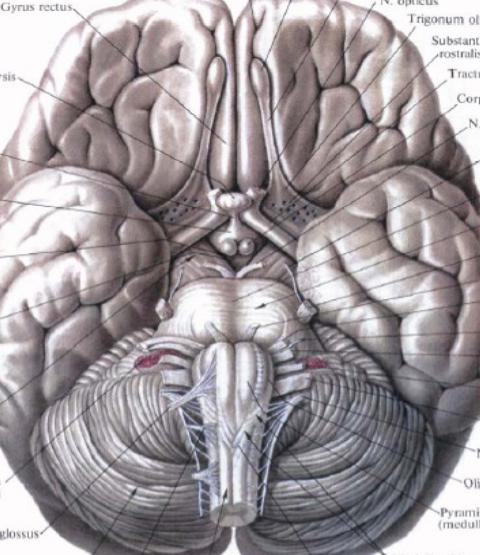

Необычные объекты: Переднее продырявленное вещество

Раздел: Альбом открытий